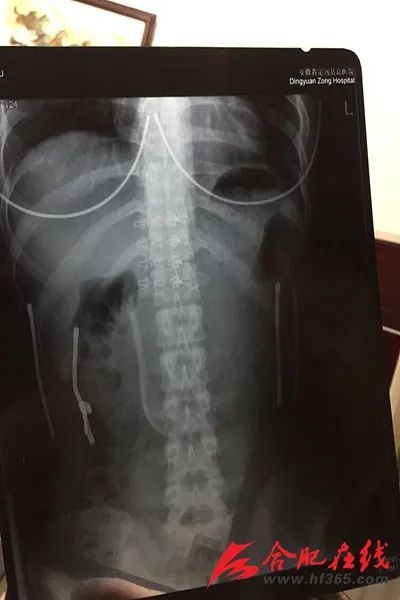

莫名其妙把勺子吞了,小雨惊慌不已。小雨的描述让当地医生吓了一跳,医生赶紧让小雨做CT检查勺子的位置。X光片显示勺子竖立卡在十二指肠降段。看着X光片里泛着幽幽荧光的勺子,小雨不禁害怕起来。在家人的陪伴下紧急转到安医大四附院消化内科就诊。

“毕竟是一个这么大的异物,不尽早取出来随时危险,勺柄尖端可刺破肠壁出血穿孔。一旦勺子再往下滑动到空肠,患者只能通过外科手术开刀取出。”安医大四附院消化内科主任唐敏介绍,医生综合评估小雨的情况后决定紧急利用麻醉胃镜进行无痛异物取出术,通过胃镜进入十二指肠到勺子卡住的位置,套住勺柄慢慢将勺子拉出来。“由于勺子竖在里面,导致十二指肠幽门球部和球降交界呈锐角,而勺子长且不能折弯,我们十分小心调整勺子的位置,将勺柄拉入软帽中,竖着拉出来。动作幅度不能太大,否则会划伤黏膜,造成二次伤害。”唐敏介绍,整个过程大概耗时二十多分钟。终于,这根历经“奇遇”的勺子重见天日,长达12厘米。